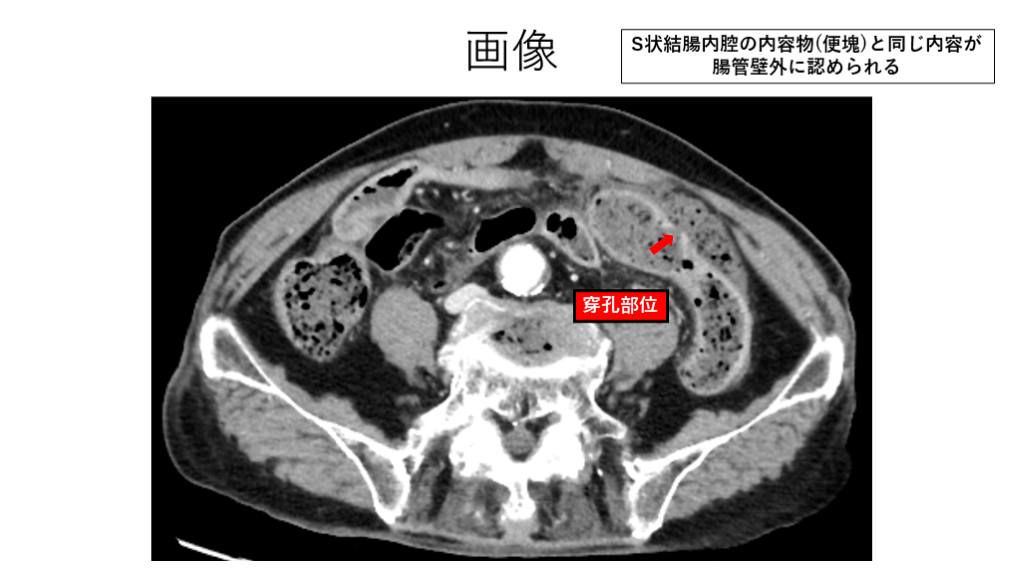

画像 S状結腸内腔の内容物(便塊)と同じ内容が 腸管壁外に認められる 穿孔部位

手術所見 S状結腸の憩室に穿孔所見あり 腹腔内は糞便で高度に汚染

診断 S状結腸憩室穿孔 汎発性腹膜炎